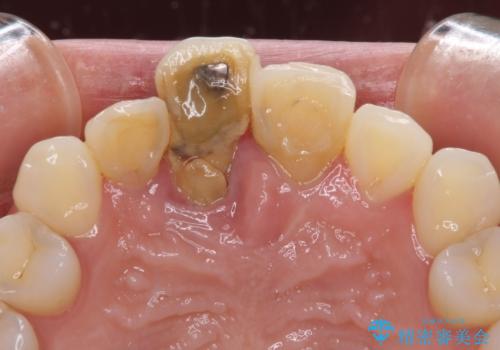

- 仮歯のまま前歯を放置しているとのことで来院された患者様です。

目視で確認できるほどしっかりとした破折が認められ、抜歯が必要と判断されました。

抜歯後は歯肉が痩せてしまうため、歯肉移植を行って歯肉の形態を改善した後、オールセラミックブリッジにて補綴することとしました。